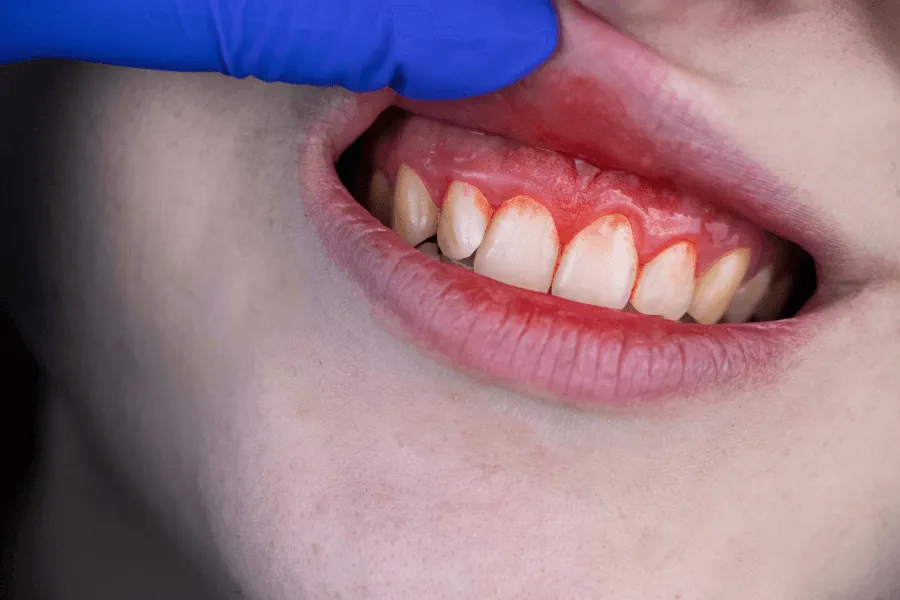

2. Zaczerwienione lub „nabrzmiałe” dziąsło

Dziąsło wokół implantu może stać się:

• intensywniej czerwone

• gładkie i błyszczące

• lekko obrzęknięte

• bardziej wypukłe niż dziąsło przy sąsiednich zębach

W mucositis kieszonki są zwykle nieznacznie pogłębione, a tkanki reagują krwawieniem - to podstawowy sygnał, że zapalenie jest aktywne.

Ocena krwawienia / wysięku

Krwawienie po delikatnym drażnieniu to najczulszy marker wczesnego zapalenia.

Lekarz ocenia:

• intensywność krwawienia

• miejsce jego występowania

• ewentualny wysięk surowiczy lub ropny

W mucositis zwykle brak jest wysięku ropnego - jeśli występuje, konieczne jest wykluczenie peri-implantitis.